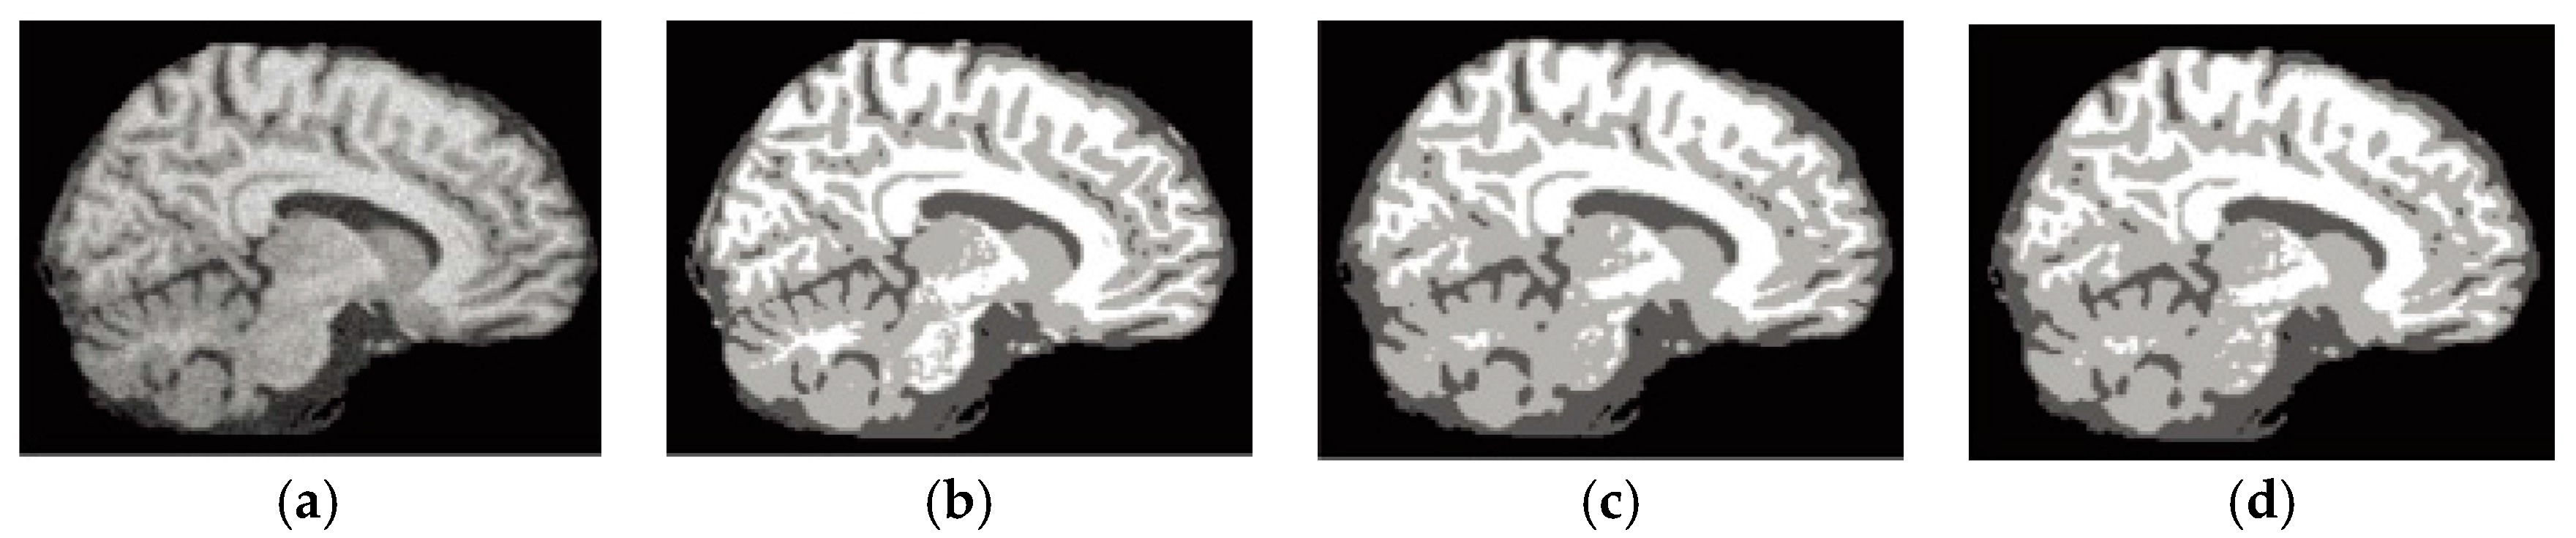

6.4. Results on Clinical Brain MR Images